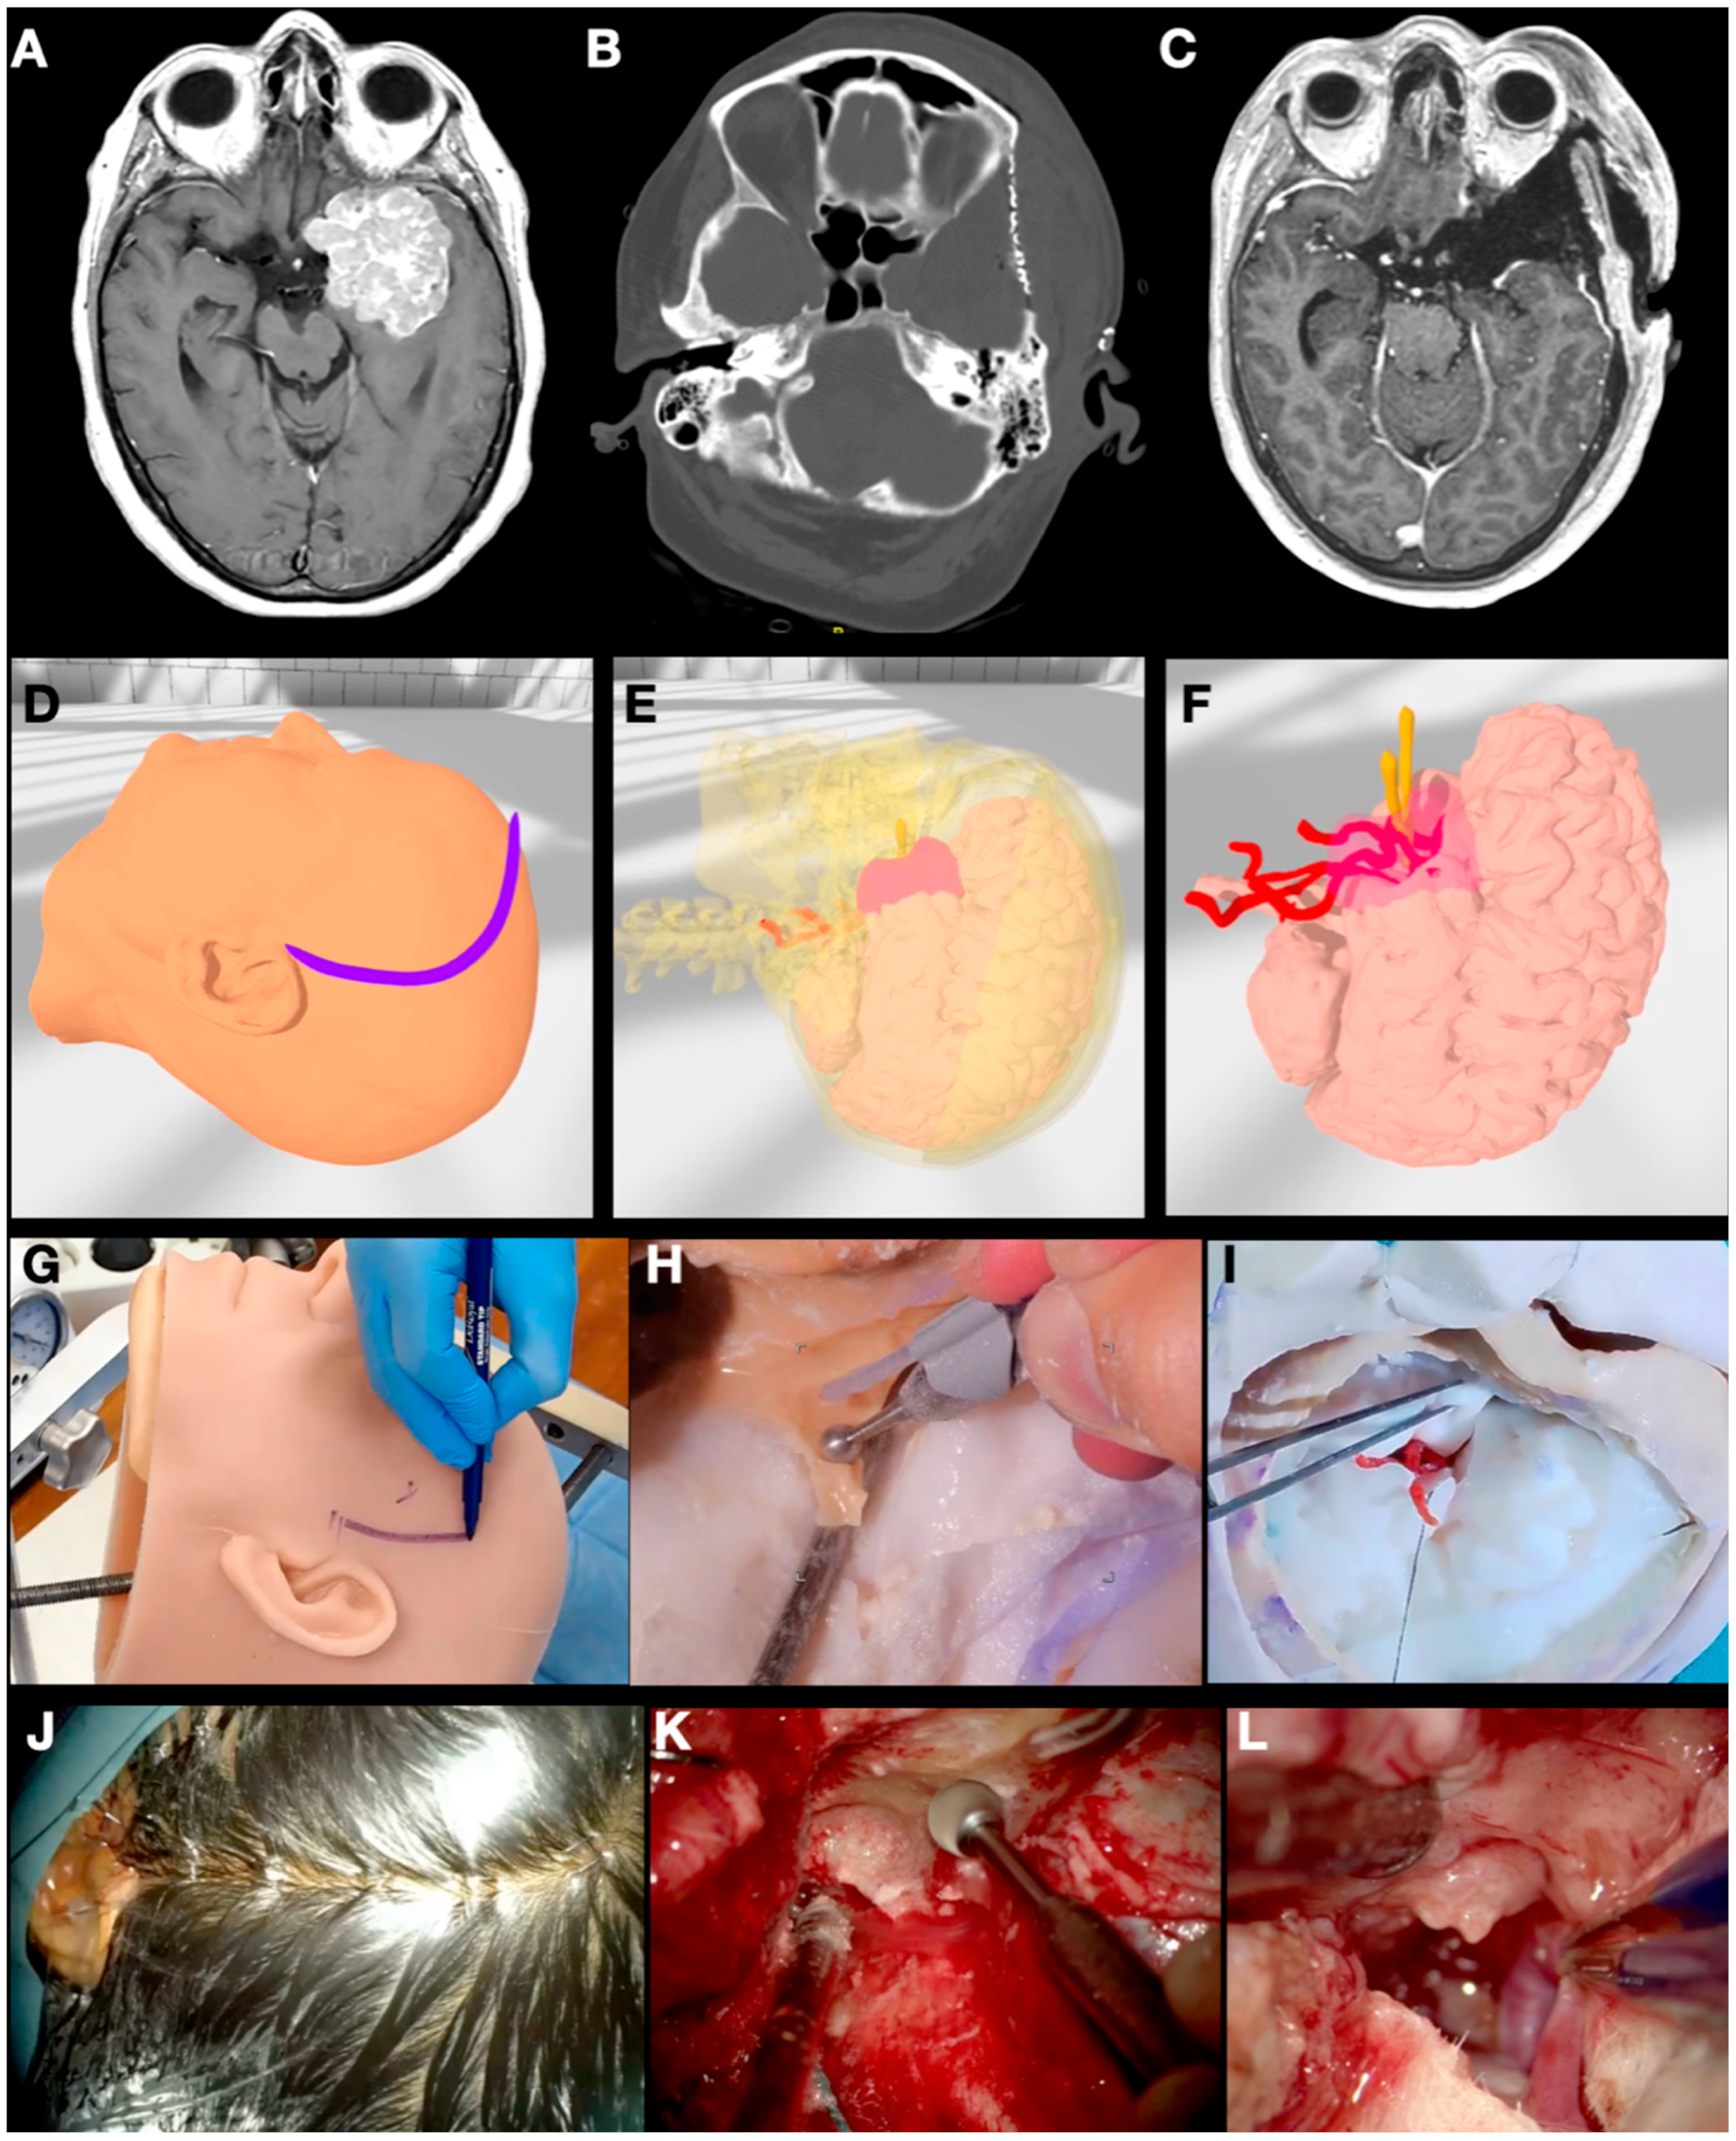

3.1. Case 1: Sphenoid Wing Meningioma